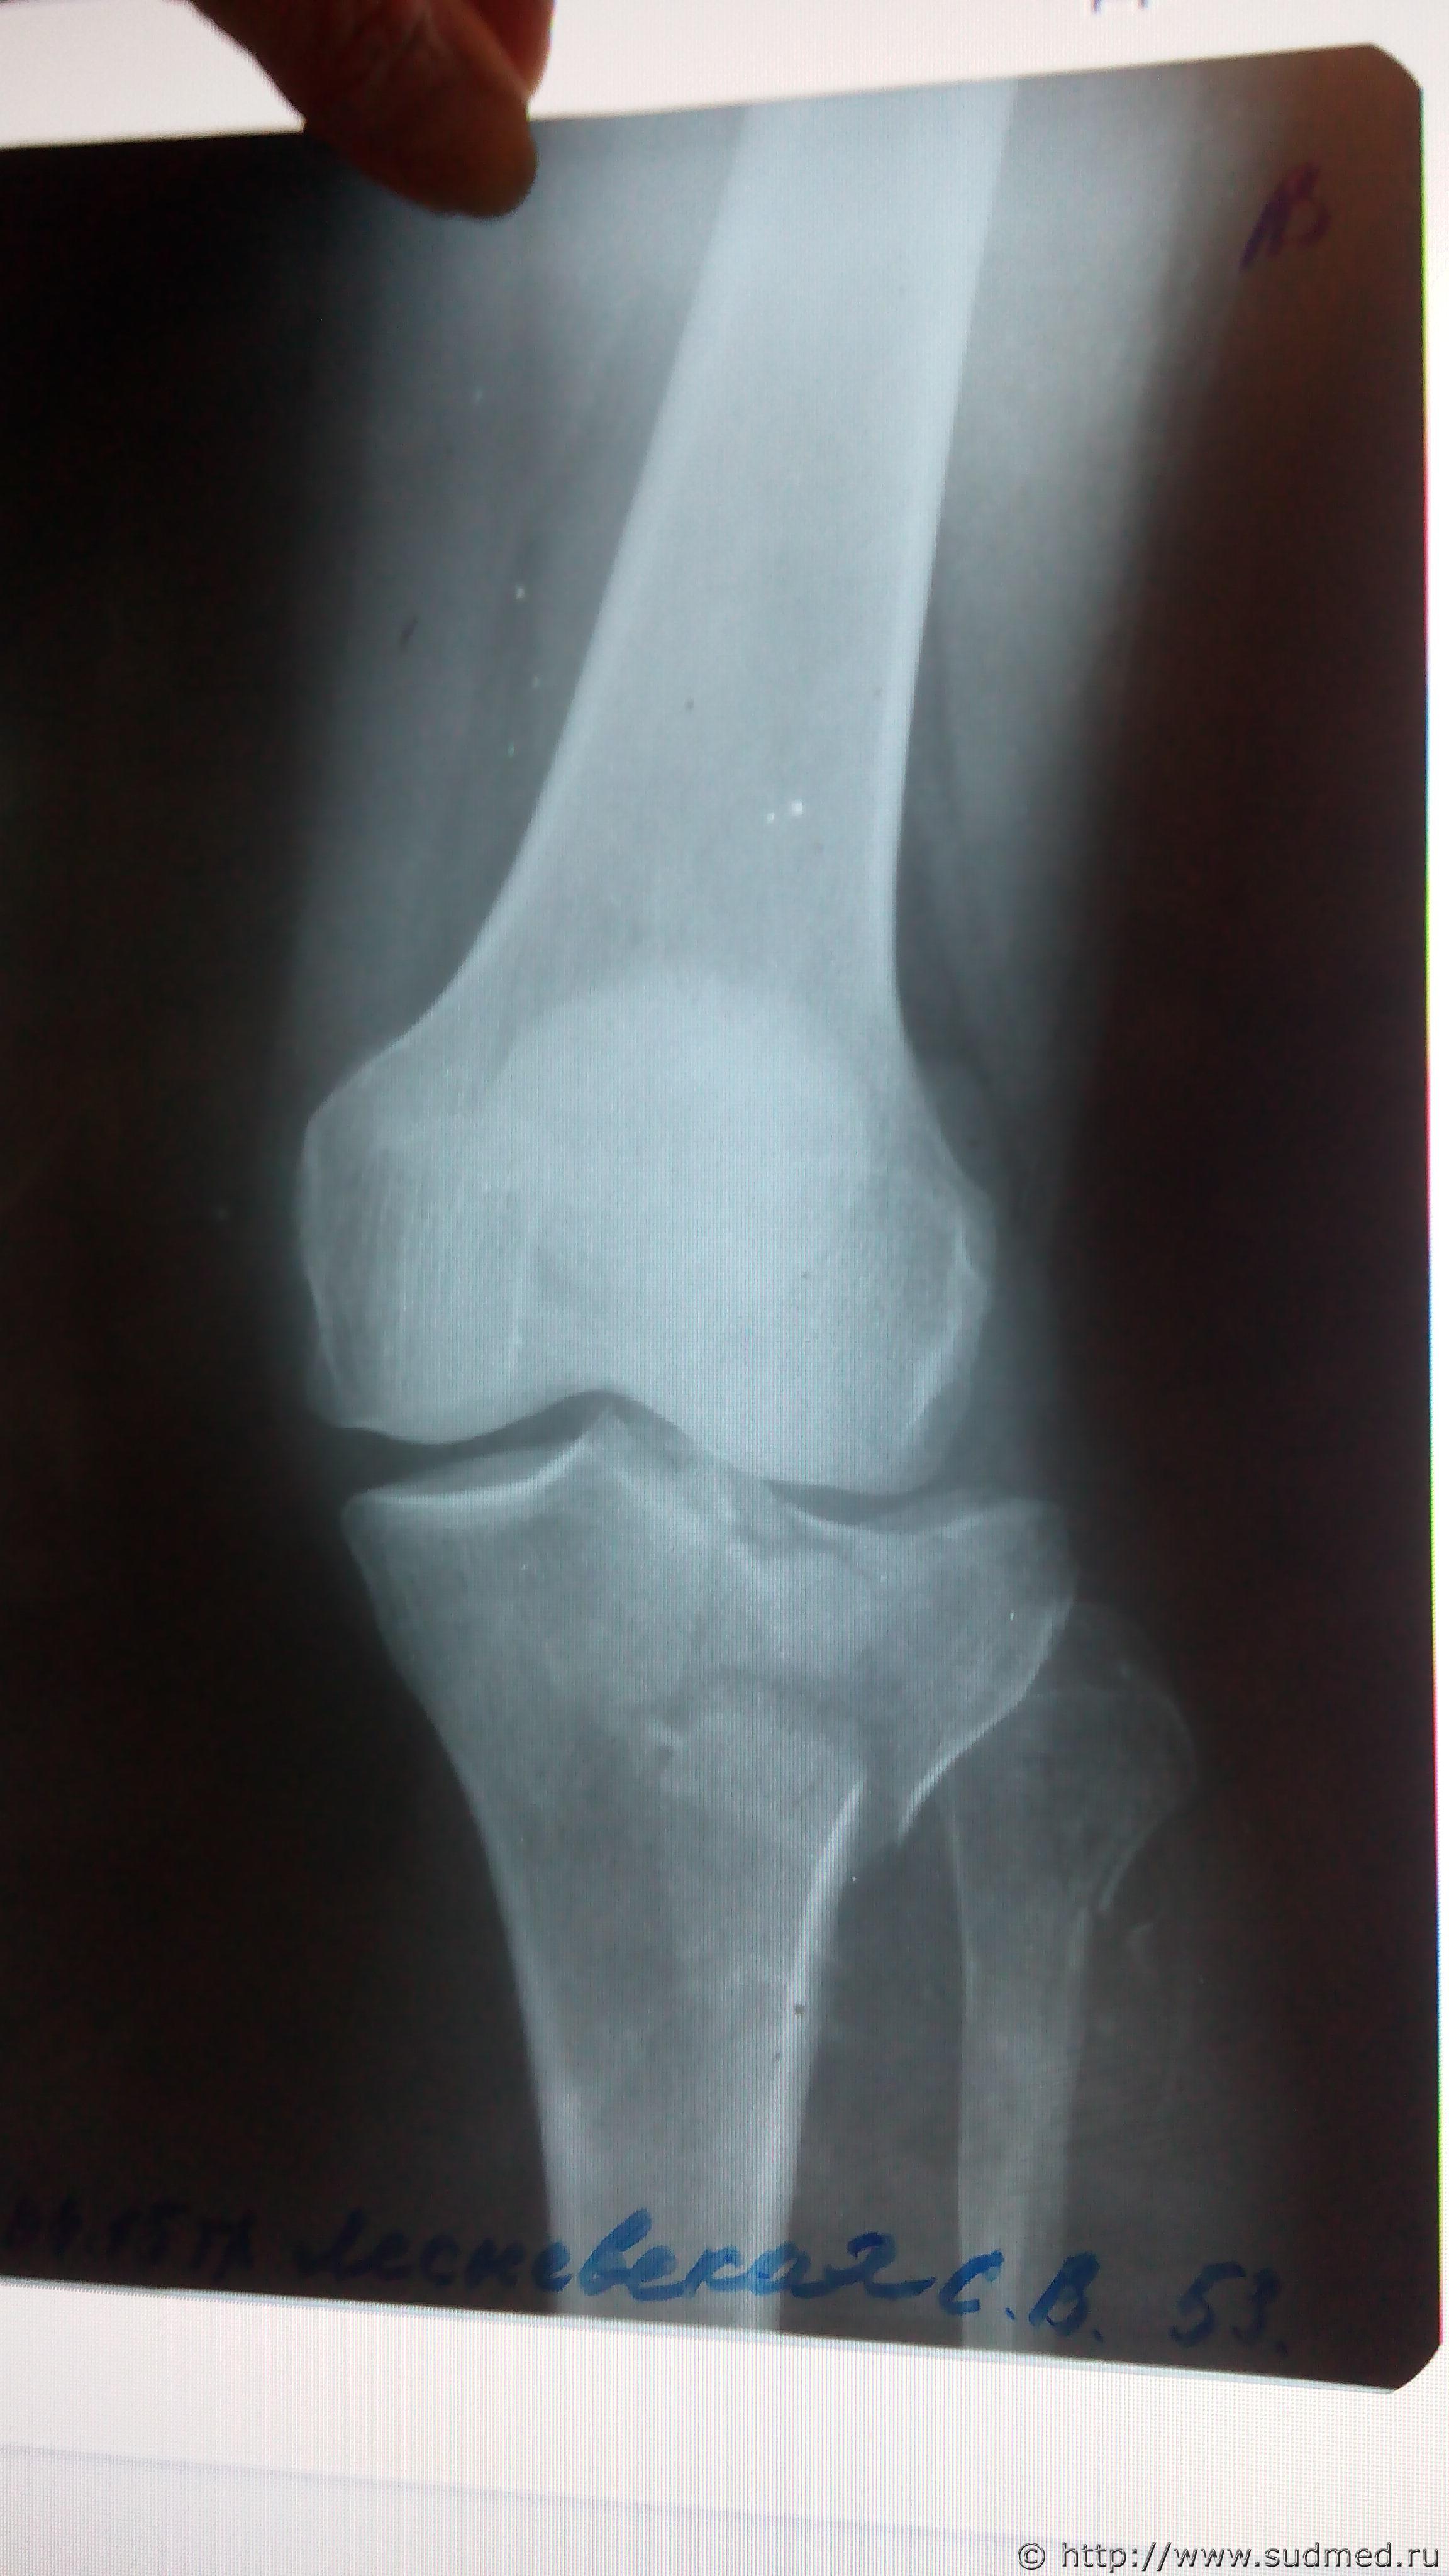

Первый рентген (до операции, 2 проекции) отсканировать есть возможность - давайте посмотрим.

Здравствуйте , постараюсь выложить снимки .

Эскизы прикрепленных изображений

Выложите все снимки. Это может быть важно: если перелом большеберцовой кости распространяется на её диафиз, то может быть тяжкий вред (п.6.11.8 приложения к Приказу Минздравсоцразвития от 24.04.08г. №194н). На единственном выложенном Вами снимке этого не видно, но зона перелома - совсем рядом с диафизом. Хотелось бы разобраться, как все обстоит на самом деле.